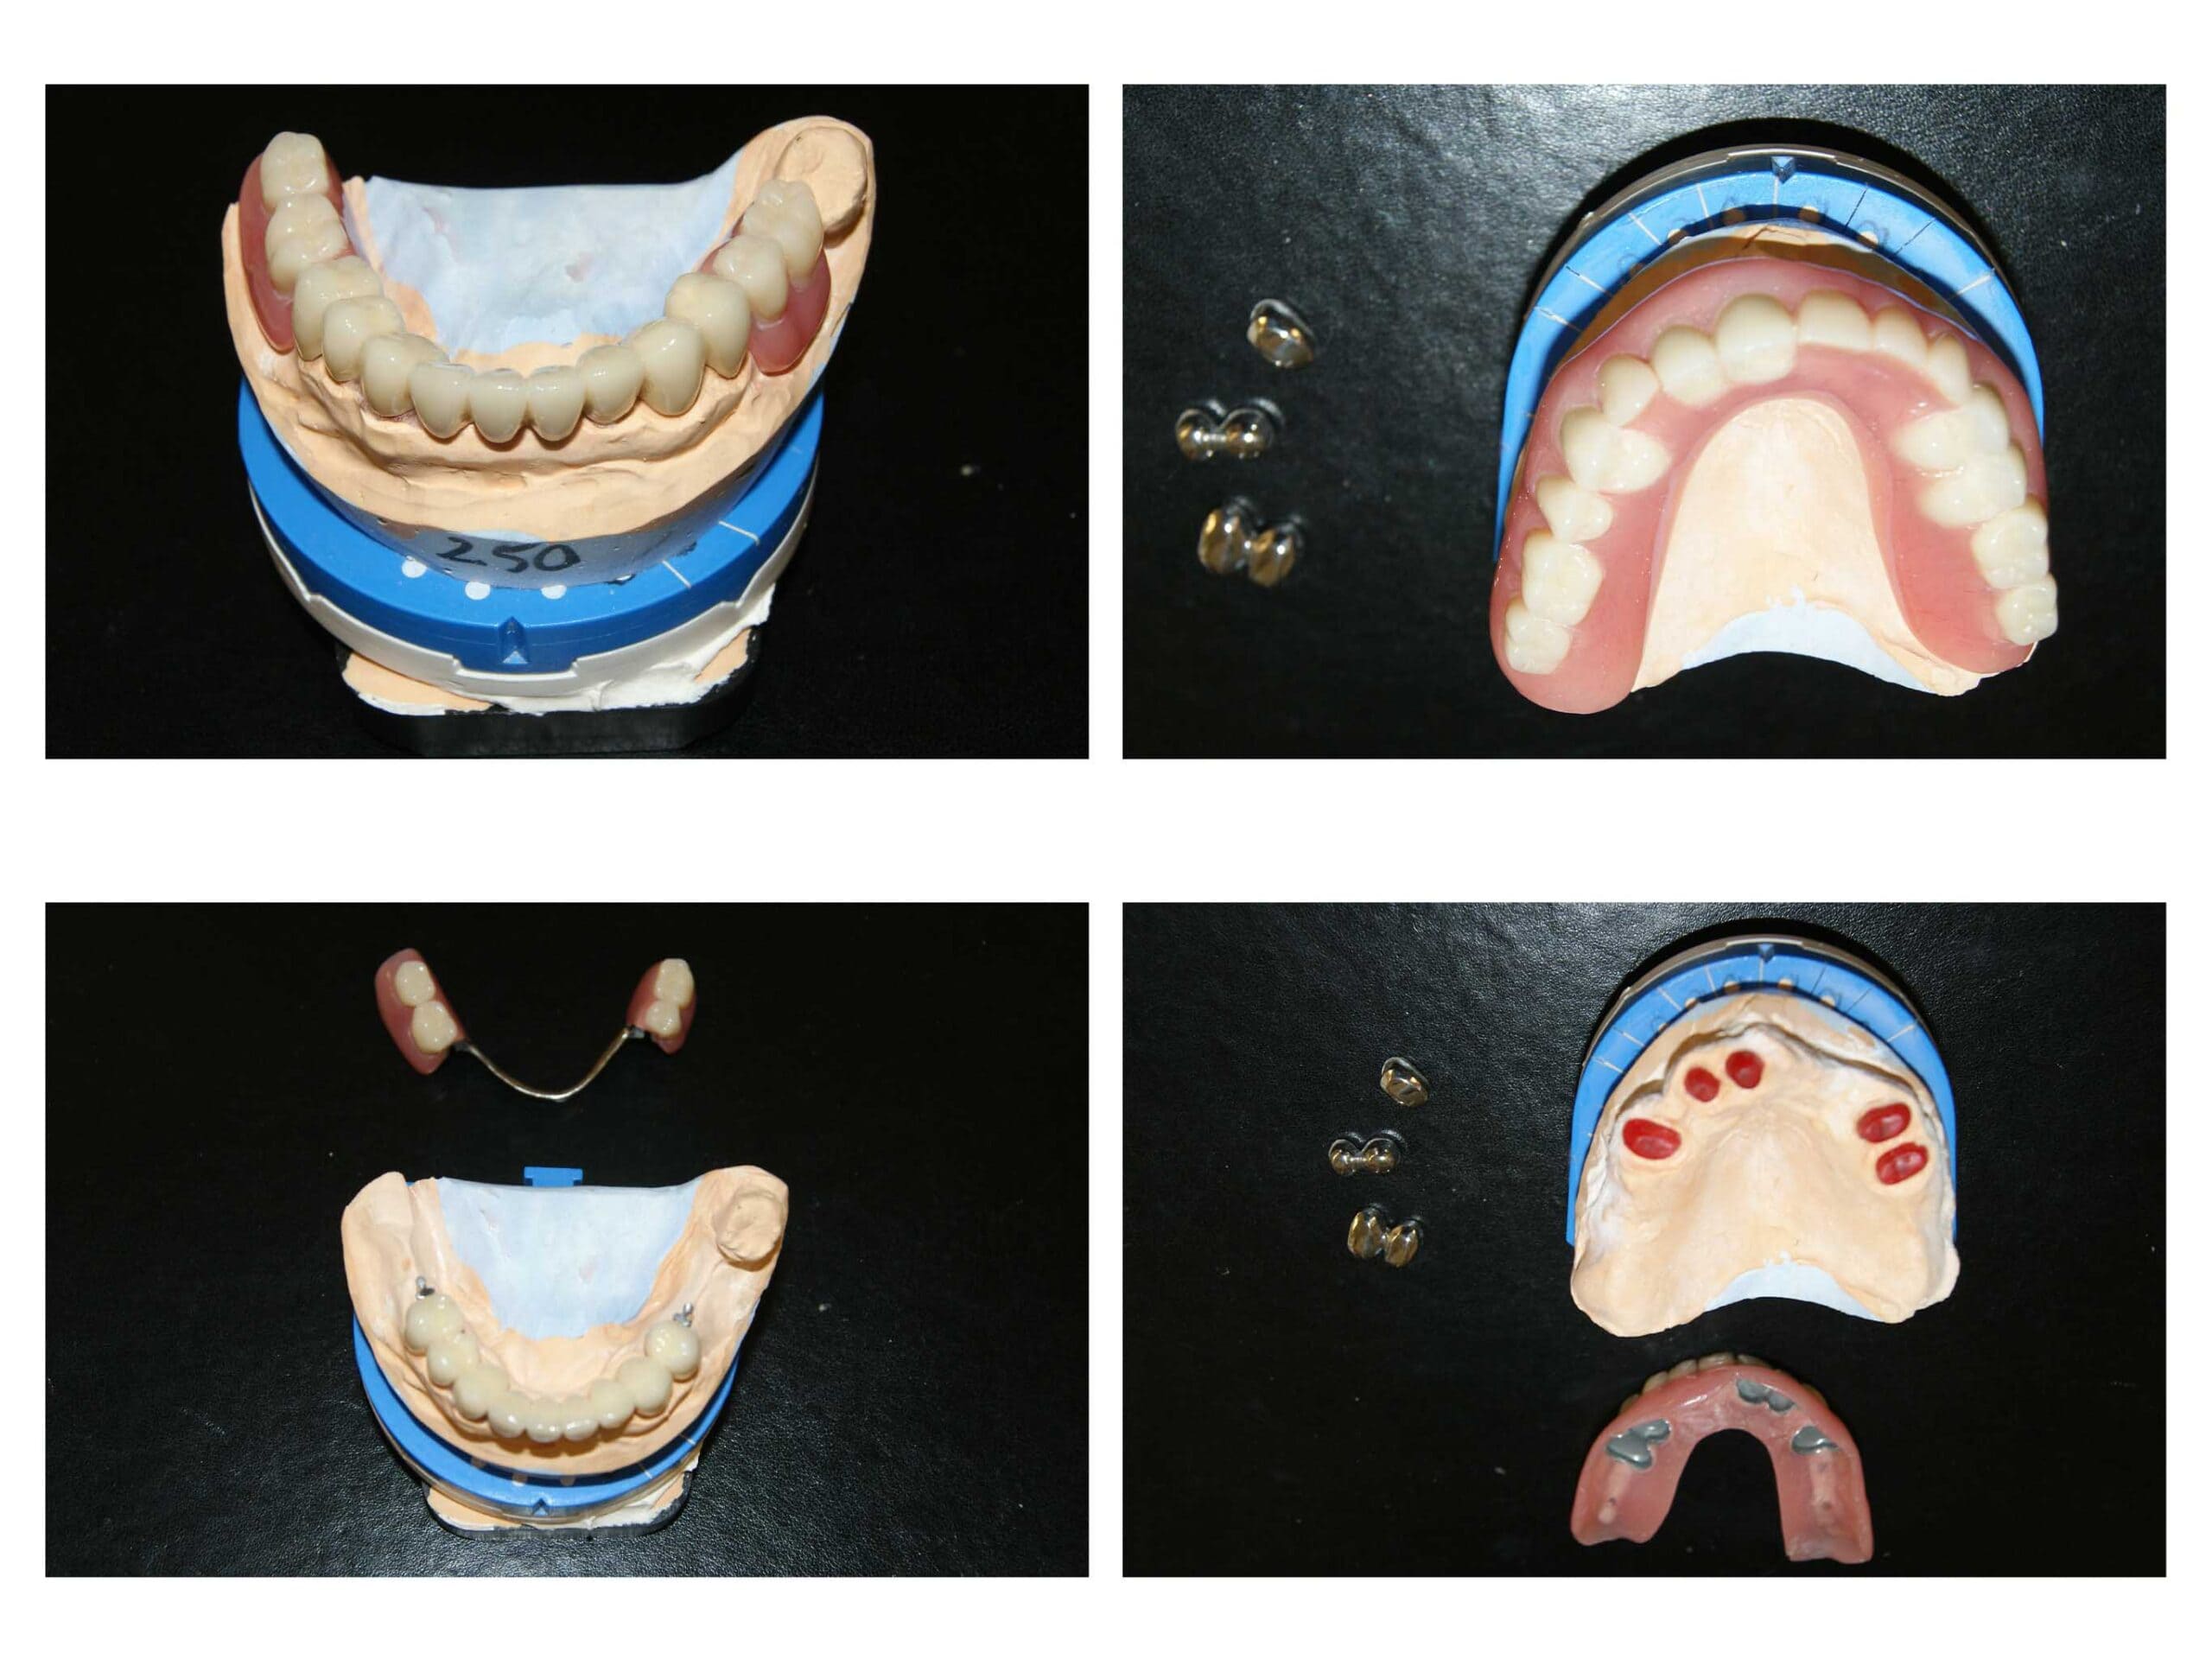

Lucrare fixată pe dinți împreună cu proteză scheletată mobilizabilă = soluția de lux pentru dinți puțini

Proteza telescopată  și proteză scheletată aplicate pe dinții tratați corect! Execuția riguroasă oferă stabilitate excelentă.